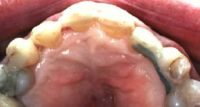

Este paciente se presentó con la queja principal de incomodidad en el funcionamiento de los dientes anteriores inferiores. Nótese la pérdida y recesión de encía.

La evidencia clínica de una enfermedad periodontal grave fue respaldada por las pruebas radiográficas en las que se observa una pérdida de hueso de más del 70% en los incisivos mandibulares y la presencia de un grado de movilidad 2 para los cuatro incisivos.

La queja principal de este paciente era la incomodidad durante el funcionamiento de los dientes anteriores inferiores. Nótese la pérdida y recesión de encía. Todos los incisivos tenían grado 2 de movilidad.

Otro factor que complicaba el caso fue que el paciente había completado dos años de tratamiento de ortodoncia para cerrar el espacio que existía en anteriores debido a la pérdida de un incisivo central por enfermedad periodontal. Hay evidencia radiográfica de pérdida de masa ósea de más del 70% en el incisivo central restante.